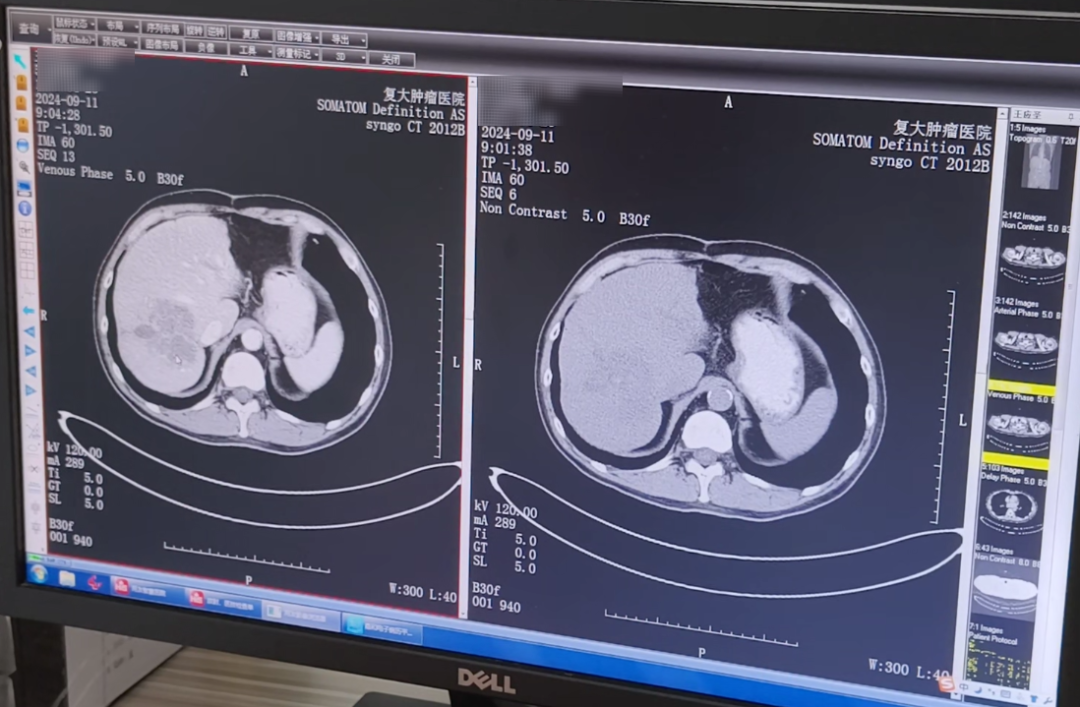

كان العم وانج، الذي دخل المستشفى للتو، يعاني من آفة نقيلية كبيرة في الفص الأيمن من الكبد، وكان حجمها تقريبًا 7.4×6.7×9.2 سم. كانت هناك العديد من العقد الليمفاوية الصغيرة في منطقة البوابة والجزء الخلفي من الصفاق، والتي تم تعزيزها بشكل كبير بعد التعزيز. بالنظر إلى التاريخ الطبي للعم وانغ والحالة الفعلية، طلب الدكتور المعالج على الفور استشارة متعددة التخصصات. بعد التقييم، قدم خطة علاجية أولية: أولاً إجراء العلاج الكيميائي التدخلي والانصمام التدخلي لتقليل تدفق الدم إلى الورم وتقليل حجمه؛ ثم قم بإجراء عملية التجميد لتقليل الحمل والسيطرة على تطور الورم.

△فحص التصوير المقطعي المحوسب أثناء أول دخول للمستشفى في سبتمبر 2024